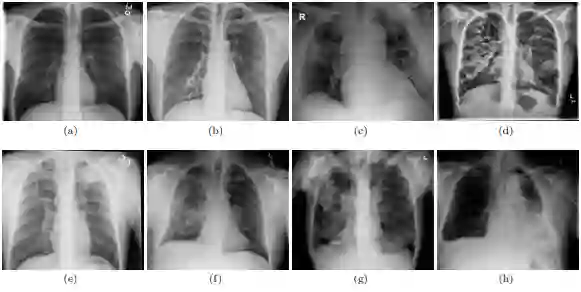

The world is going through a challenging phase due to the disastrous effect caused by the COVID-19 pandemic on the healthcare system and the economy. The rate of spreading, post-COVID-19 symptoms, and the occurrence of new strands of COVID-19 have put the healthcare systems in disruption across the globe. Due to this, the task of accurately screening COVID-19 cases has become of utmost priority. Since the virus infects the respiratory system, Chest X-Ray is an imaging modality that is adopted extensively for the initial screening. We have performed a comprehensive study that uses CXR images to identify COVID-19 cases and realized the necessity of having a more generalizable model. We utilize MobileNetV2 architecture as the feature extractor and integrate it into Capsule Networks to construct a fully automated and lightweight model termed as MobileCaps. MobileCaps is trained and evaluated on the publicly available dataset with the model ensembling and Bayesian optimization strategies to efficiently classify CXR images of patients with COVID-19 from non-COVID-19 pneumonia and healthy cases. The proposed model is further evaluated on two additional RT-PCR confirmed datasets to demonstrate the generalizability. We also introduce MobileCaps-S and leverage it for performing severity assessment of CXR images of COVID-19 based on the Radiographic Assessment of Lung Edema (RALE) scoring technique. Our classification model achieved an overall recall of 91.60, 94.60, 92.20, and a precision of 98.50, 88.21, 92.62 for COVID-19, non-COVID-19 pneumonia, and healthy cases, respectively. Further, the severity assessment model attained an R$^2$ coefficient of 70.51. Owing to the fact that the proposed models have fewer trainable parameters than the state-of-the-art models reported in the literature, we believe our models will go a long way in aiding healthcare systems in the battle against the pandemic.